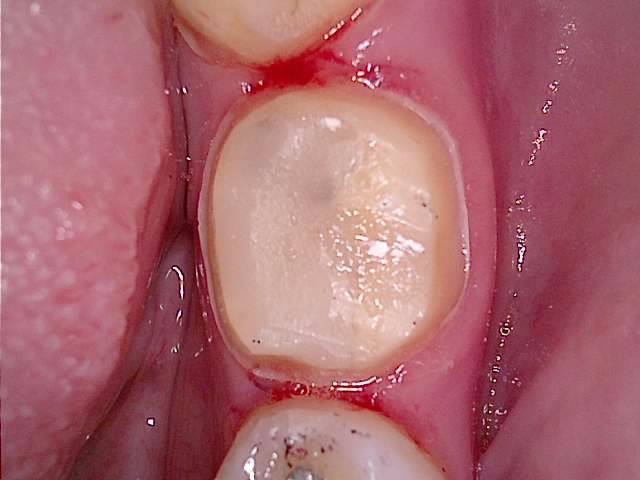

5. 크라운 접착 — 치료 결과

시린 증상과 통증이 없음을 확인한 뒤 크라운을 접착합니다.

크라운 치료 후 상악 교합면 — 아말감 교체 부위 크라운 접착 완료 사진

▲ 크라운 접착 완료 — 상악 치료 결과